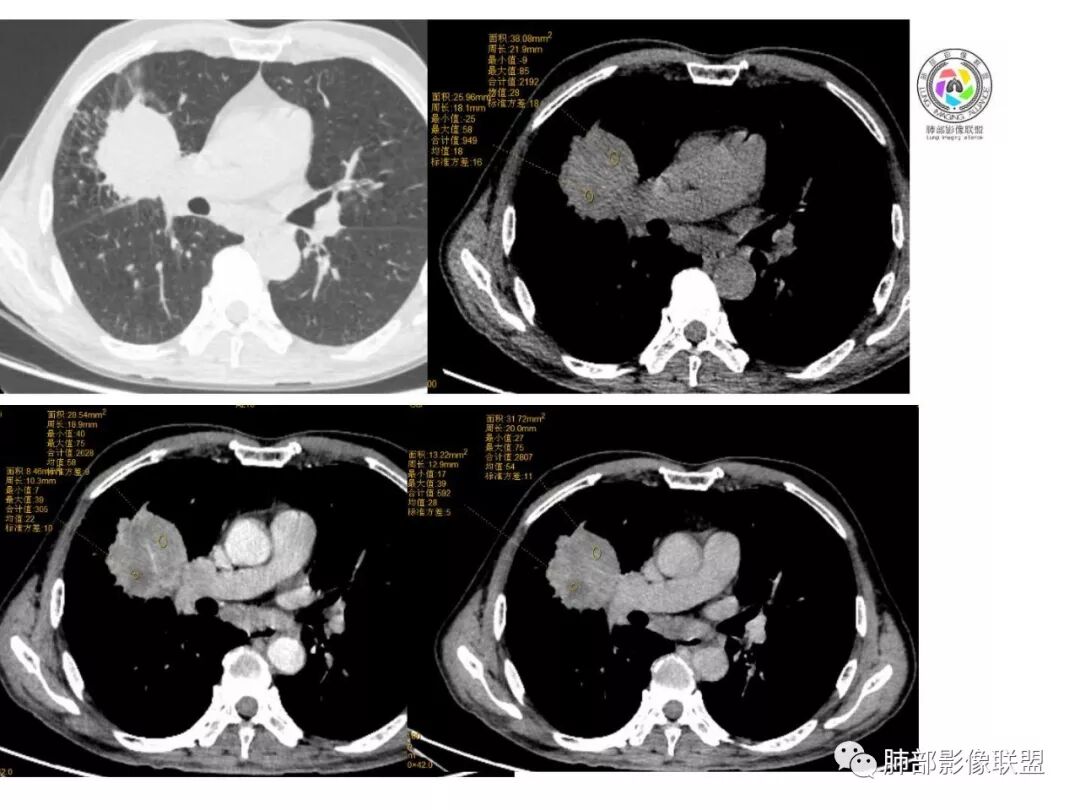

患者中老年男性,体检发现右肺占位。血常规轻度贫血,AFP、CEA正常,肝肾功能、血糖、血脂、心肌酶、电解质正常。胸部CT:右肺中叶巨大肿块灶,垮叶生长,可见分叶、毛刺、血管集束、支气管截断征象,远端周围可见小叶间隔增厚,增强轻度强化,内可见低密度坏死区,综合淋巴结肿大,且可见淋巴结内似低密度灶。综合考虑恶性,鳞癌并癌性淋巴管炎可能大。鉴别结核、腺癌。

右肺中叶巨大肿块,外侧段近端支气管截断,横跨上中下三叶,主体在中叶,膨隆分叶,毛刺,网格,淋巴结大,不均匀强化,伴阻塞性肺炎及肺不张,湖泊样坏死,考虑恶性,鳞癌可能性较大

右肺中叶肿块影,向上向下侵犯叶间裂,边缘膨隆,分叶,毛刺。肿块内部密度不均,大片坏死。血管走形尚可。中叶支气管狭窄截断。增强不均匀强化。纵隔淋巴结肿大,部分融合。

考虑恶性,腺癌>鳞癌。鉴别炎肌母。